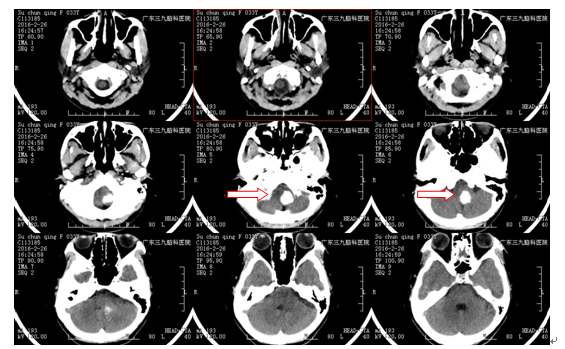

治疗:入院后完善术前准备,于2016-3-2行脑干占位性病变切除术,术中见脑干延髓区肿瘤,向左外侧生长,血供一般,边界欠清,大部分钙化明显。给予镜下大部分切除肿瘤,术后给予抗炎、营养神经等对症治疗,予预防感染、止血、营养神经等康复治疗,术后病理检查提示:毛细胞星形细胞瘤(WHOI级)。

经治疗,患者头晕明显改善,无恶心、呕吐,无肢体抽搐,无发热等不适,查体:神志清醒,正确对答,双侧瞳孔3mm,光反射灵敏,双侧咽反射略减退,咳嗽反射稍差,心肺腹未见明显异常,四肢活动良好。患者术后存在轻微后组颅神经症状,并未出现严重颅神经功能损害,经综合康复治疗后总体恢复较好。

脑干肿瘤早期一般不易被发现,尤其是低级别胶质瘤或海绵状血管瘤未出血时期,一般不引起脑干神经核团或颅神经功能损害表现,故大部分病人早期会被漏诊。一旦发现,最好手术治疗,以明确病理为主要目的,同时在术中电生理监测、术中导航引导下尽可能多切除肿瘤,注意操作仔细,避开颅神经、脑干神经核团,尽可能减少由于颅神经损害带来术后并发症。该病例主要特点为病变强化不明显,并且钙化为主,术前不存在明显颅神经损害症状,术中行肿瘤基本切除,术后患者恢复比较理想,病理提示I级胶质瘤,预后良好。